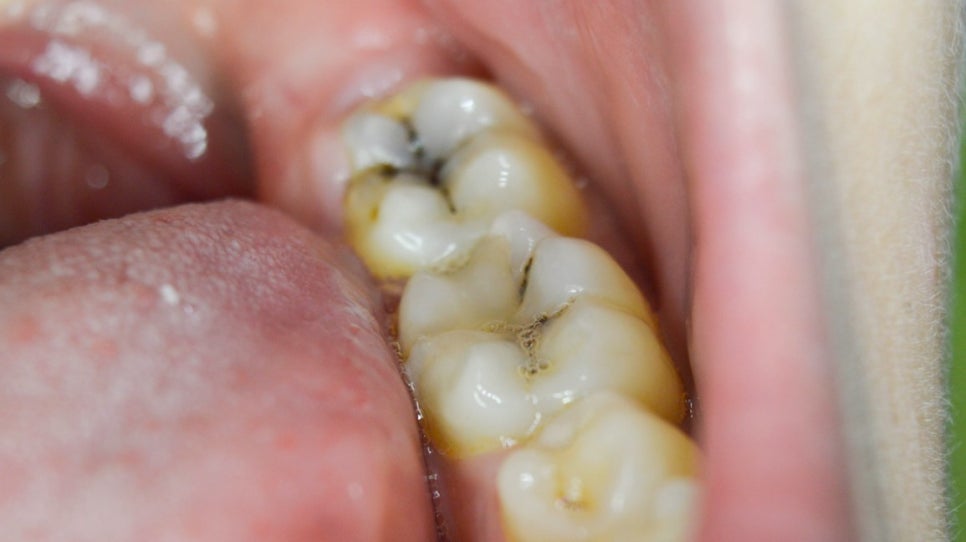

충치는 치아 관리를 잘 한다고 해도 많은 분들이 경험하고 있을 정도로 쉽게 생기지만, 대수롭지 않게 생각하여 방치하면 문제가 점점 커지기 때문에 초기에 치료하시는 것이 굉장히 중요합니다. 통증이 없다고 하더라도 반드시 주기적인 검사와 치료를 받으시는 것을 권장해 드립니다.

음식물 섭취에 따라 구강에 남아있던 음식물이 세균과 결합하여 치아우식증이 발생하는데 당분이 많은 사탕, 과자, 음료수 등을 자주 드시는 경우 당연히 확률이 더 높아집니다. 또한, 양치질을 열심히 하여도 발생한 충치가 개선되지는 않습니다.

충치는 법랑질에서 시작하여 내부로 퍼지는데 정도가 심해지면 통증을 동반하게 됩니다.

초기에는 법랑질에 한정되어 우식증이 생기는데 이 때는 증상이 없는 경우가 대부분입니다.

다음 단계로는 상아질까지 진행이 되는데 겉으로는 작은 점처럼 보이더라도 치아 내부로 넓게 진행이 된 경우가 많고, 차거나 뜨거운 음식을 먹을 때 불편해 지거나 통증을 느끼게 됩니다.

치수까지 (치아의 신경) 염증이 진행되면 통증의 정도는 더욱 심해지고, 자극이 없더라고 통증이 생기는 단계가 됩니다.

마지막으로, 뿌리까지 염증이 진행된다면 잇몸뼈를 파괴시키고, 심한 경우에는 치아를 발치해야 합니다.

치료는 레진, 인레이, 크라운 등을 사용하여 수복을 하게 되는데, 환자분들의 건강상태 및 우식증의 원인, 진행정도를 고려하여 판단합니다. 간단한 경우에는 병변 부분을 긁어내고 충전물을 채워 쉽게 치료할 수도 있지만 치수까지 진행이 된 경우 신경치료가 동반됩니다. 이때 신경치료를 한 치아는 쪼개질 위험이 있기 때문에 어금니라면 반드시 크라운을 씌워야 합니다. 적절한 시기에 치료를 놓치게 되면 자연치아를 소실할 수 있고, 임플란트 등의 대체 방안이 필요하게 됩니다.

보존 치료 방법으로는 레진, 인레이, 크라운, 세라믹 등이 있는데 치아의 손상정도와 환자의 상태 등에 따라 사용가능한 방법이 달라질 수 있습니다. 예전에 많이 사용하던 아말감의 경우에는 색감 등의 단점으로 심미성이 좋지 않고 접착력이 좋지않아 탈락, 파절 등의 이슈가 있어 요즘에는 많이 사용하지 않는 편입니다.